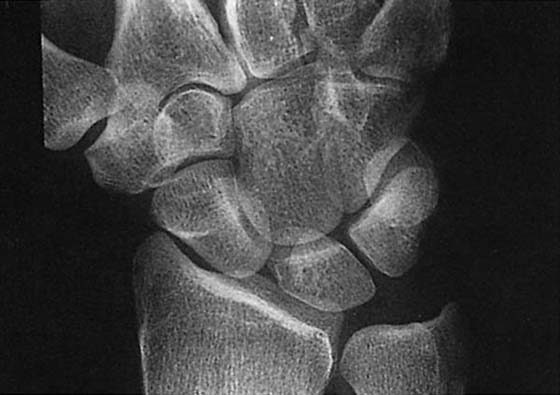

images

Figure 13-5 Posteroanterior views of the wrist demonstrating the hallmarks of rheumatoid arthritis: osteopenia, which may be the earliest sign of the disease (compare with normal bone density in Fig. 13-1, A), loss of articular cartilage, and erosions. In this patient, erosion is evident at the ulnar styloid (arrow).